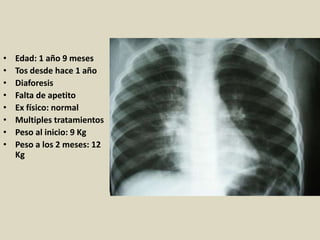

• Edad: 1 año 9 meses

• Tos desde hace 1 año

• Diaforesis

• Falta de apetito

• Ex físico: normal

• Multiples tratamientos

• Peso al inicio: 9 Kg

• Peso a los 2 meses: 12

Kg

•Edad 6 años

•Tos de 1 año

•Falta de apetito

•PPD: 10 mm